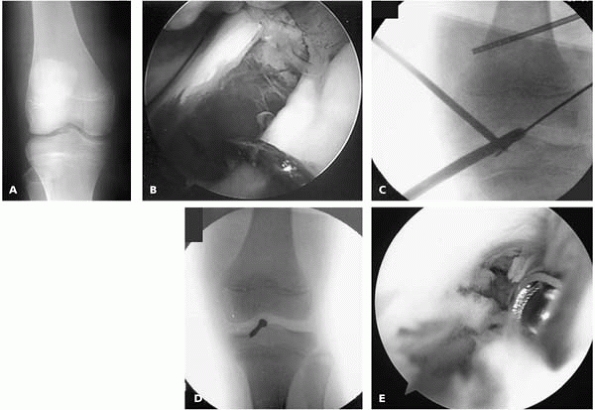

▪ FIGURE 12-7 A:

AP radiograph of another boy sent to the sports medicine center weeks after sustaining a “knee sprain.” The tibial spine fracture, evident as subtle fragmentation in the intercondylar notch, was missed by the initial treating physician. He had pain and motion loss. B: Arthroscopic view after best attempt at manual reduction. C: Intraoperative radiograph as the guidewire for a cannulated screw is being placed. D: Intraoperative radiograph after screw placement. E: Despite stable fixation and early mobilization, the boy developed debilitating arthrofibrosis. Arthrofibrosis can be a major source of trouble after treatment of tibial spine fractures. |